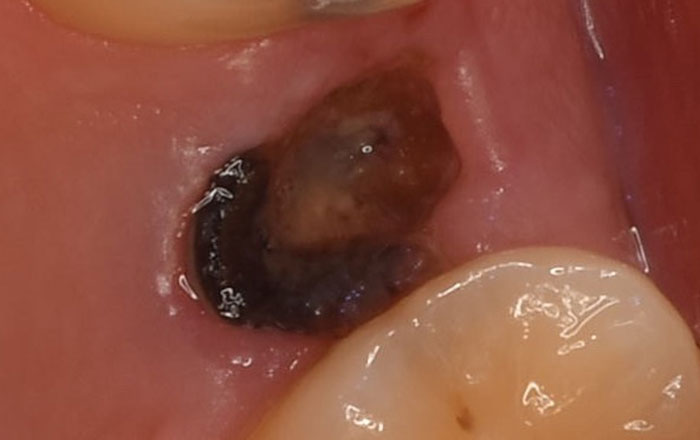

5.C4のむし歯

C4のむし歯は、歯の頭の部分がなくなり、根っこのみ残っているむし歯です。

神経が破壊されて死んでしまっているので、痛みが軽くなったり、もしくは痛みがないことが多いです。この状態は、ばい菌が他の疾患を引き起こす可能性もあります。

この段階の治療方法は、基本的には抜歯が必要となります。

歯を残せる場合もありますが、クラウンレングスニングなどの外科的な処置が必要となることが多いです。歯のない部分は、インプラント・ブリッジ・入れ歯のいずれかでで歯のない部分を補う必要があります。